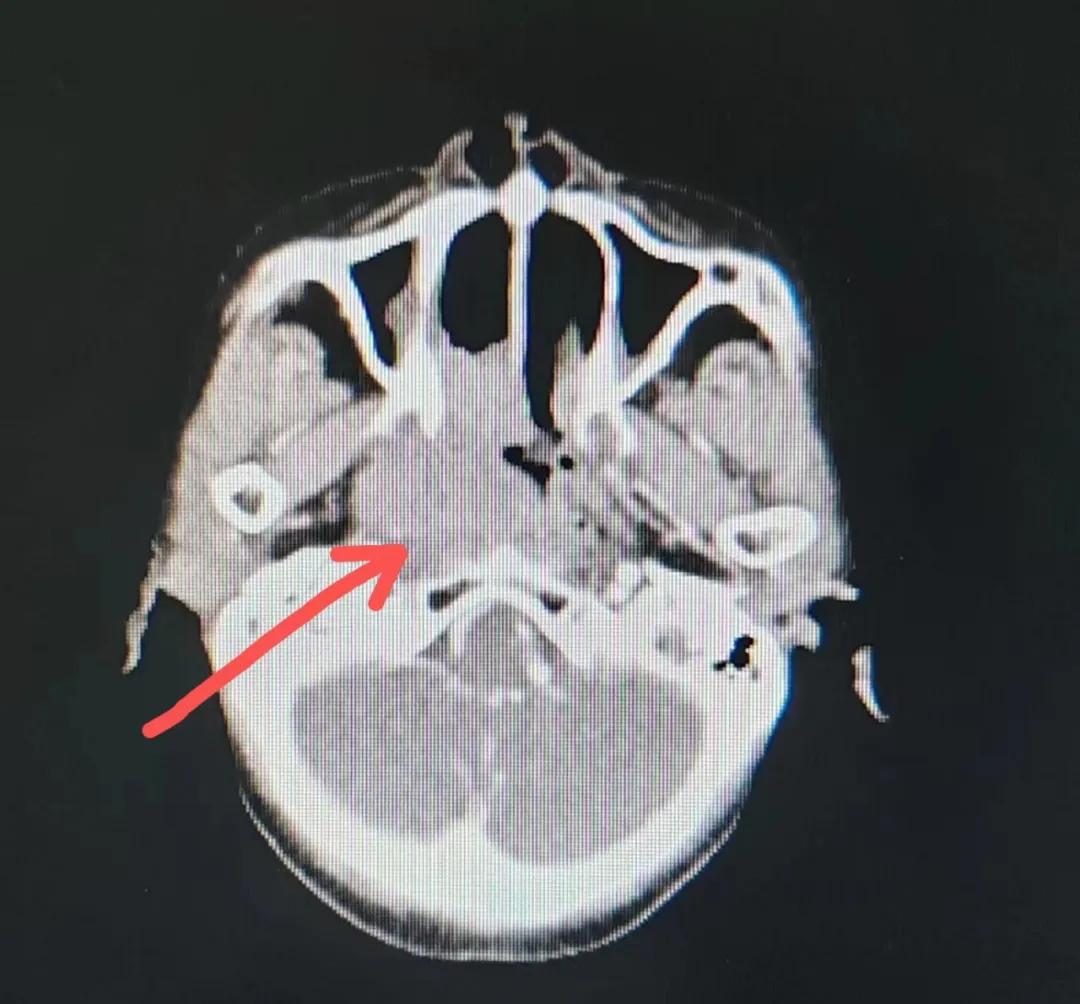

治療后

放療結束,除了放療處的皮膚輕微放射性皮炎外,基本沒有什么不良反應。復查發(fā)現(xiàn),鼻腔淋巴瘤已不可見,目前患者已康復出院。